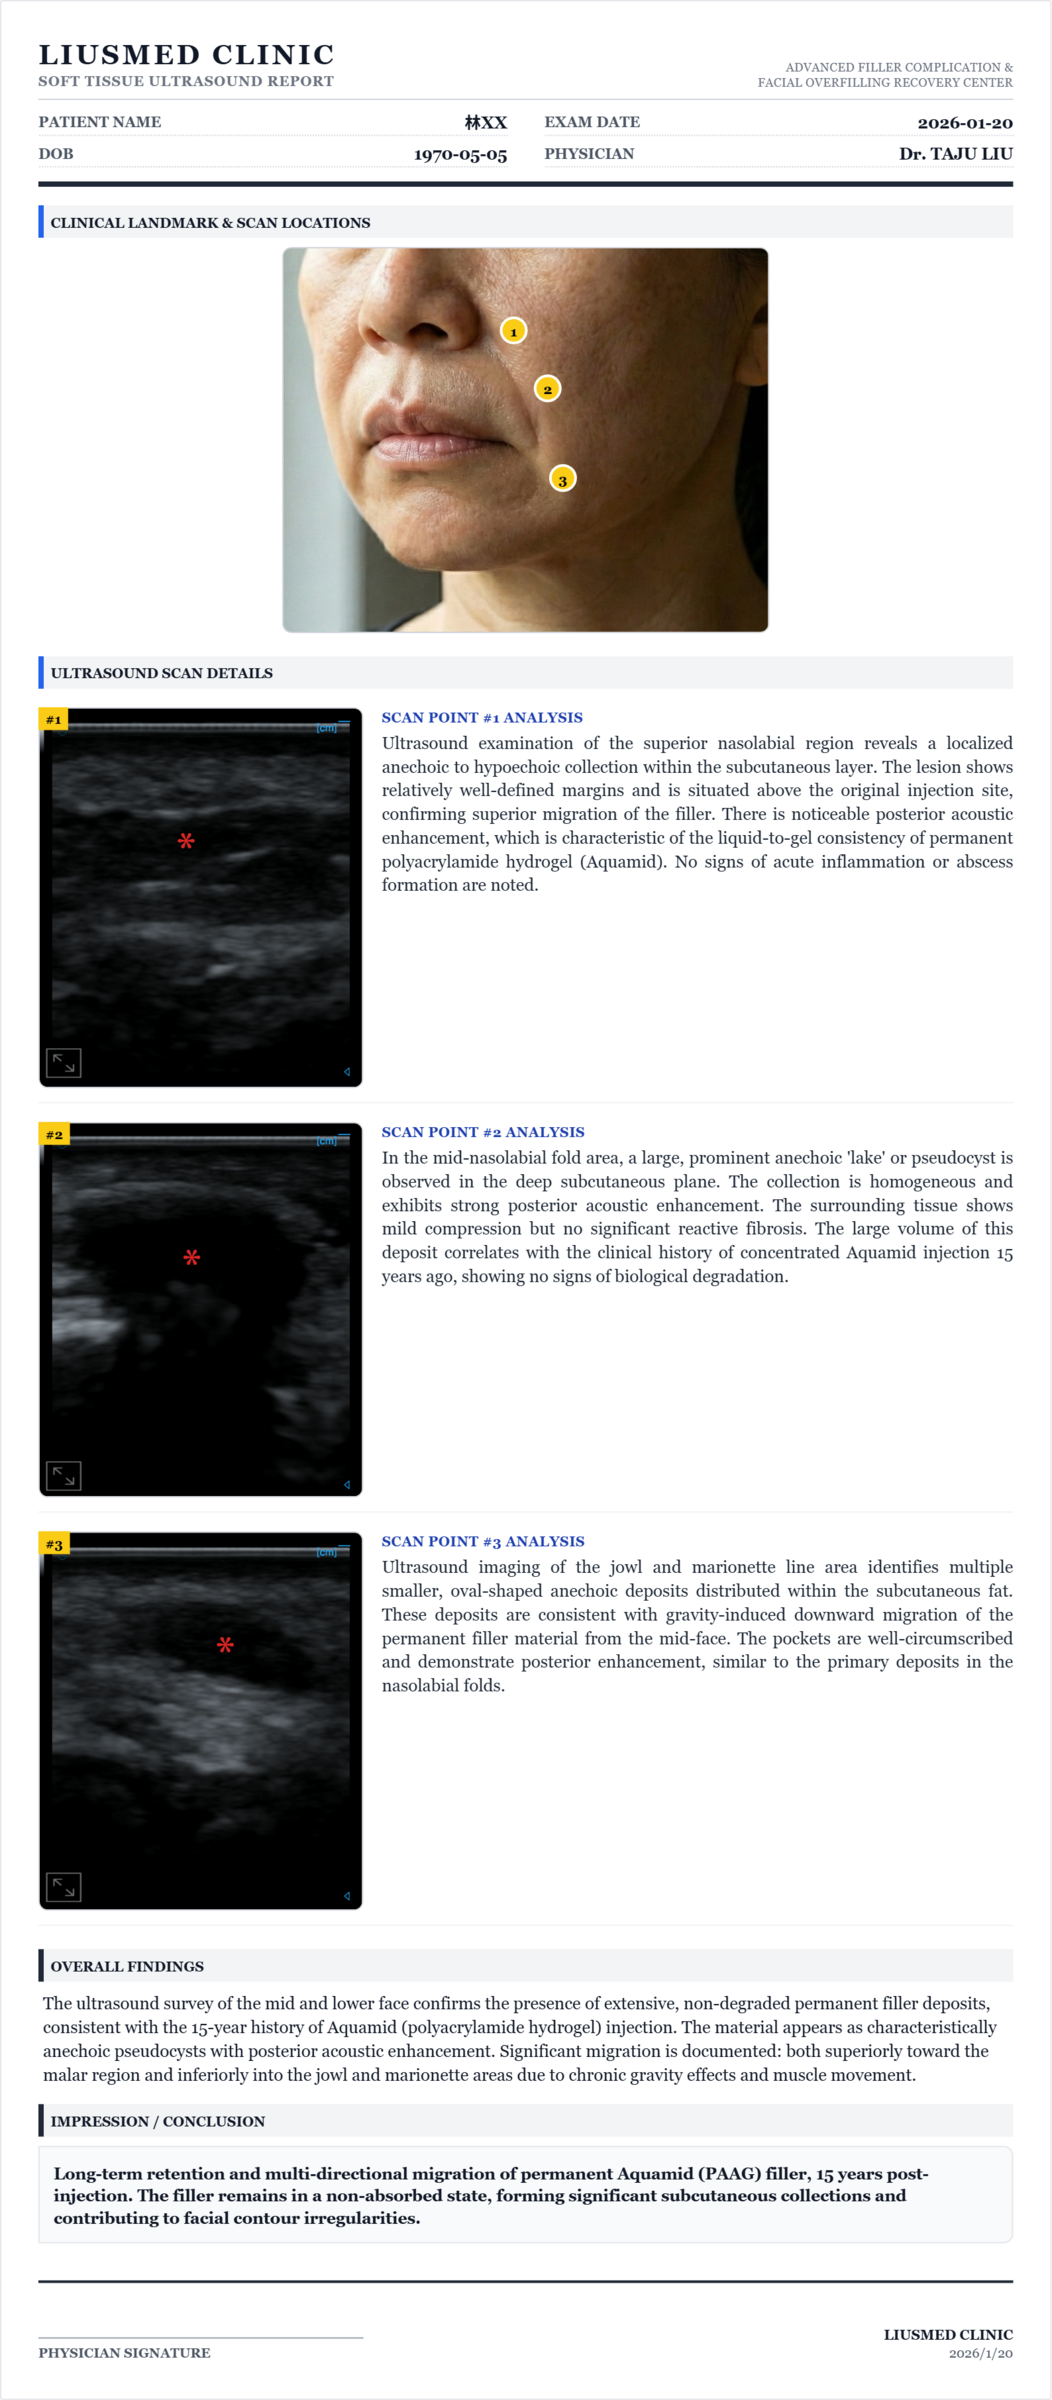

Permanent Filler Can Be Removed! Aquamid Migration Extraction Record

This case reveals two critical facts often overlooked. First, permanent fillers can be extracted. Aquamid injected 15 years ago shows as a classic "pseudocyst pool" on ultrasound with zero degradation. Using high-resolution ultrasound guidance and micro-pinhole technique, we safely extracted it in segments without traditional wide-incision surgery. Second, fillers migrate. Imaging clearly shows this permanent material didn't stay in the nasolabial folds — it migrated upward toward the nasal ala and downward toward the marionette lines, driven by years of gravity and facial muscle activity. This explains why some patients feel their face "looks increasingly off" without being able to pinpoint why.